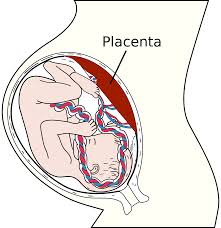

- Com 19 semanas de gestação, a mamãe agora já começa a sentir o peso da barriguinha, devido a junção do bebê, líquido amniótico e placenta.

Como a mamãe está se sentindo

Com 19 semanas de gestação, a mamãe agora já começa a sentir o peso da barriguinha, devido a junção do bebê, líquido amniótico e placenta. O bebê já começa a pesar, e senti-lo começa a ficar muito perceptível para algumas mulheres. Para as mamães de 1ª viagem a sensação é como se tivessem 100 borboletas dentro da barriga! É bem sutil no início, mas de agora em diante os movimentos começam a ficar cada vez mais vigorosos e fortes e ficam muito mais perceptíveis a sua mão e aos sentidos.

Estou com a placenta Posterior e próxima o orifício ulterino precisando afastar placenta previa na idade adequada. Pode me explicar